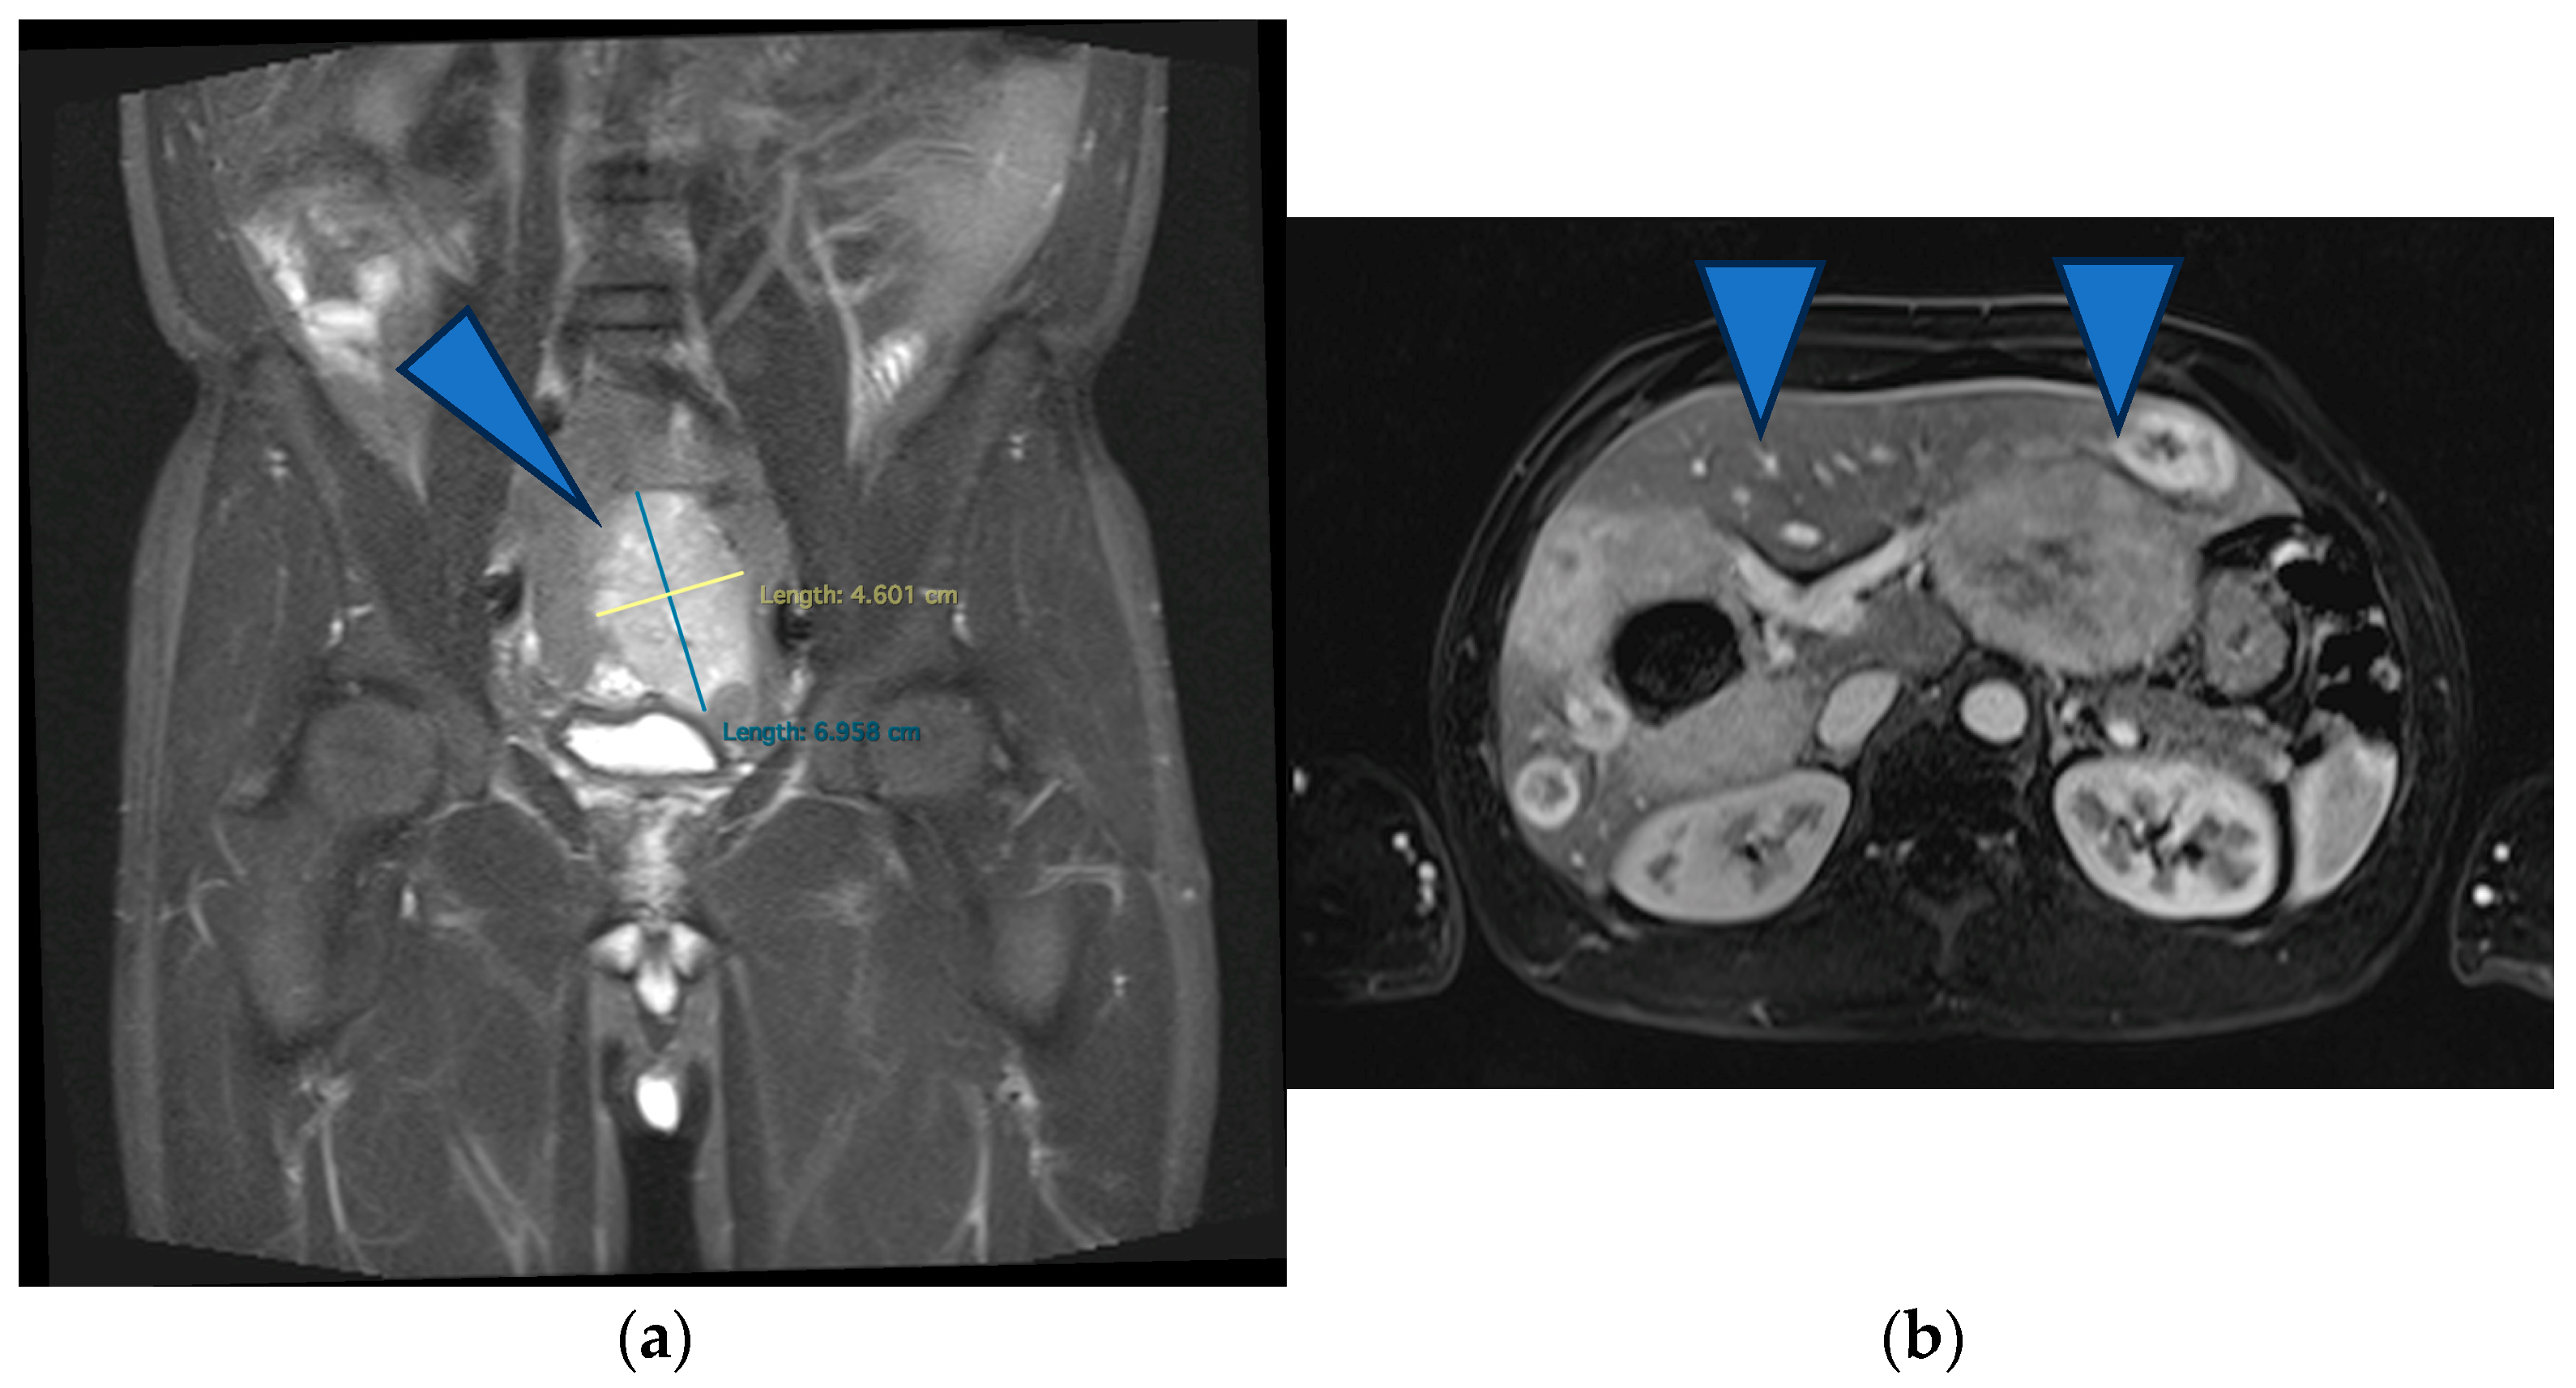

At this time, the treatment goal (set by a multidisciplinary team) was palliative because of the great disease burden in the liver, which was considered unresectable, and also because the ileal tumor did not show any acute complications (Hb = 9.3 g/L after administering 1 MER). Therefore, TKI therapy was initiated (Imatinib, 400 mg daily). The oncological follow-up at 2 months of TKI therapy showed a partial response according to the Choi criteria (the primary tumor measured 5.6 cm, and the liver metastases were stationary). Five months later, the primary tumor began to bleed significantly; therefore, emergency surgery involving a segmental ileal enterectomy with end-to-end anastomosis was performed. The preoperative MRI revealed stable disease according to the Choi criteria (Figure 2). The histological exam revealed an ileal gastrointestinal stromal tumor 6 cm in size, with a mitotic index greater than 5/50 HPF, with positive CD 117 and a Ki-67 Index of 25%, staging pT3 pN1 pM1hep (Figure 3).

Figure 2.

(a) MRI showing stable disease according to the Choi criteria of the primary tumor (arrowhead) (b) and of the liver metastases (arrows).